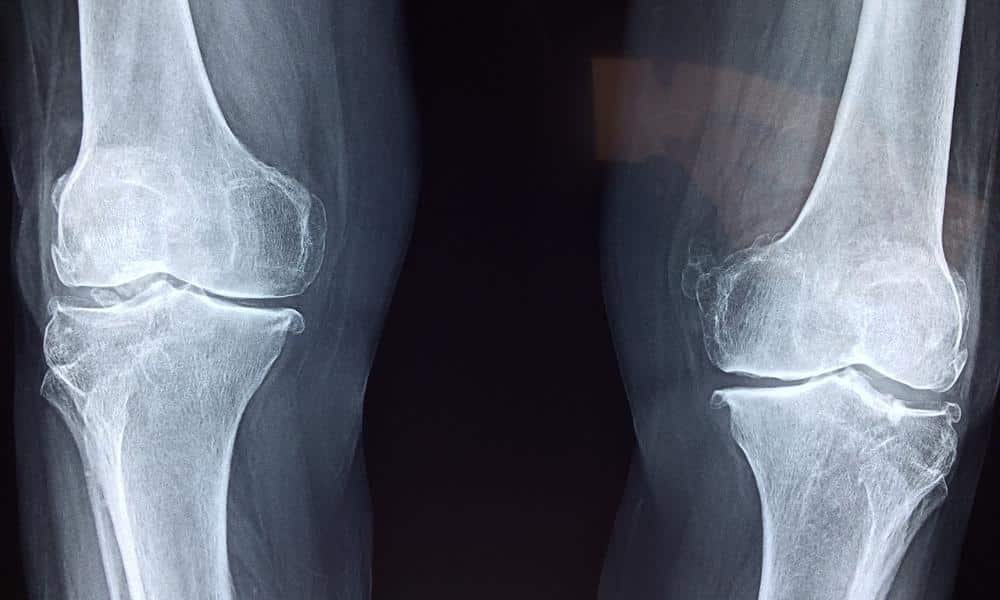

Badania ortopedyczne – profilaktyka kontuzji

Nie ma sportowca, który nigdy nie doznał kontuzji. Regularne badania ortopedyczne pomagają w wykrywaniu ewentualnych problemów ze stawami, mięśniami i więzadłami. Wśród najczęściej wykonywanych badań ortopedycznych znajdują się badania rentgenowskie, USG stawów oraz badania MRI w przypadku bardziej skomplikowanych urazów. Dzięki takim badaniom sportowiec może w porę zdiagnozować mikrourazy, które w przeciwnym razie mogłyby prowadzić do poważniejszych kontuzji.